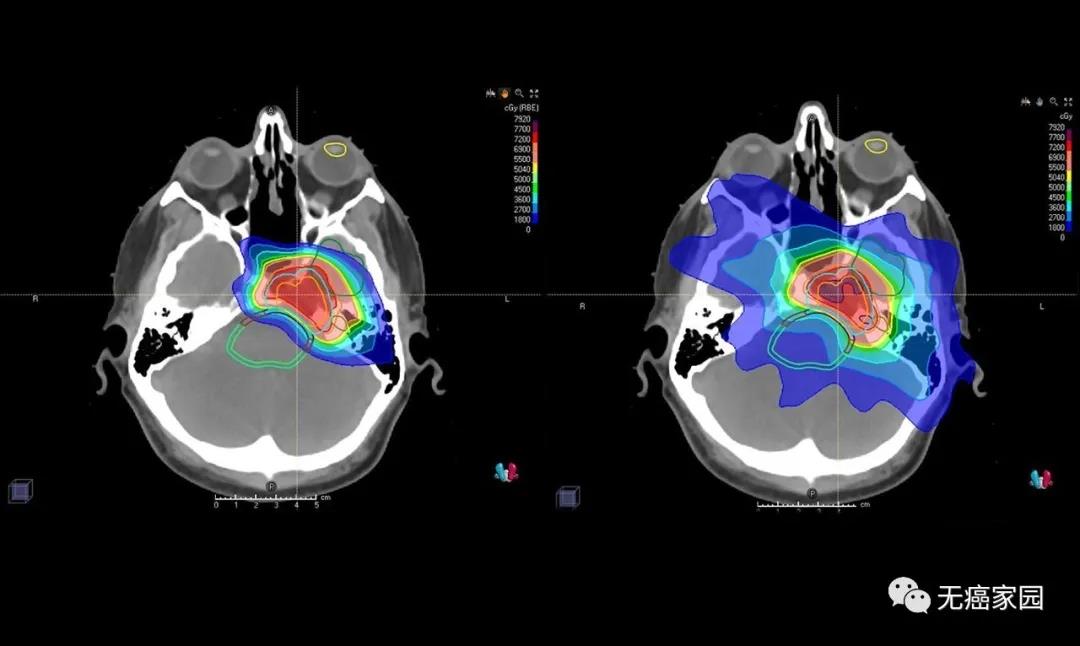

近期,约翰·霍普金斯·金梅尔癌症中心的权威质子中心医学主任,医学博士Christina Tsien在其官方平台上表示,质子疗法能够提供...

近年来,肿瘤的放疗新技术层出不穷,像伽玛刀、射波刀、质子刀等等。让饱受肿瘤折磨的患者对这些“刀”充满的希望,但是对这些“刀&r...